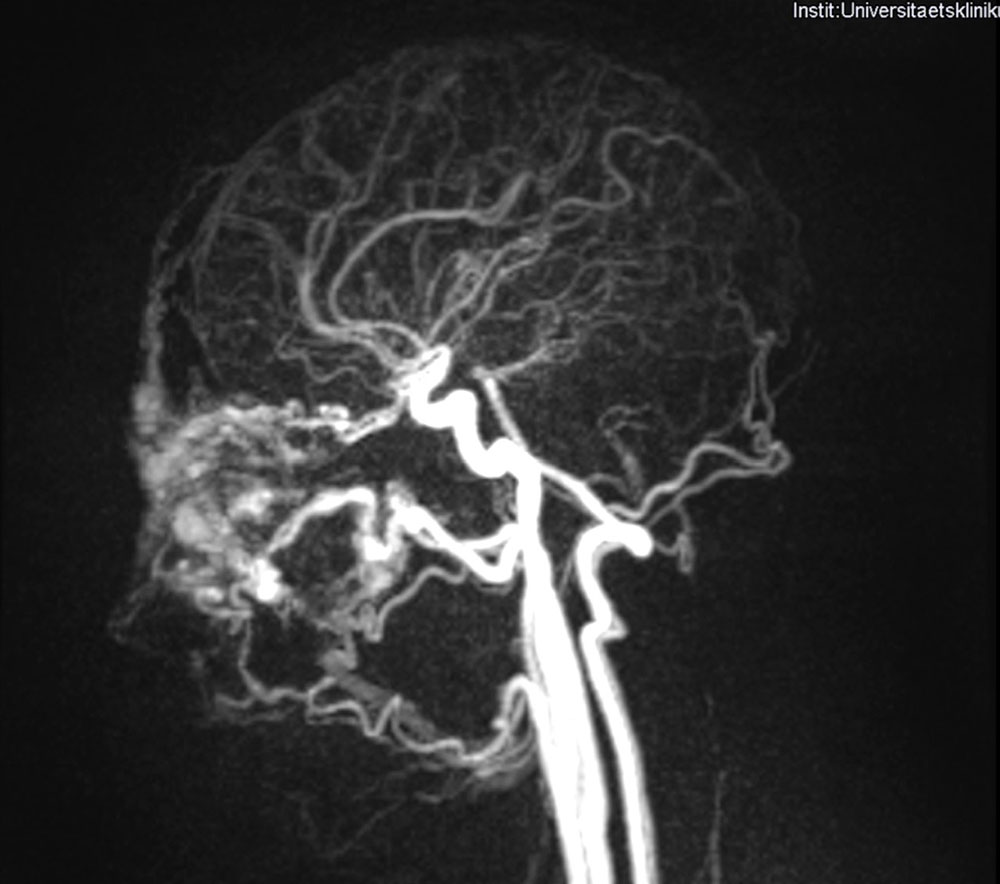

This example shows that, after an operation 15 years earlier, revision is possible with equal success. The reappeared arteriovenous malformation, which had gained in dynamics in the time before the operation demonstrated here, was covered with a local flap plasty after embolization. To cover the expected tissue deficit without tension, a skin expander was inserted close to the malformation and successively filled. The diseased tissue was removed and covered with a local flap, taking into account the position of the eyebrows.

Postoperatively, the patient experienced a good cosmetic and functional result.